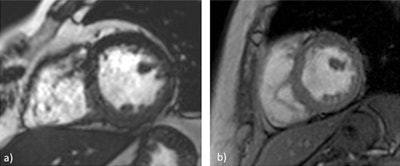

Speaking from experience, Brandão pointed to cardiac MRI, which relies on fast imaging and patient cooperation. Cine imaging is usually made with steady-state free precession (SSFP) pulse sequences, which are prone to susceptibility effects arising from lung-heart interfaces, or in patients with pleural effusion. The heterogeneity of the main field leads to local variations of the SSFP signal and dark-band artifacts.

"There are possible solutions to this problem. These include ensuring the lowest possible repetition time, performing localized high-order shimming to reduce those steady-state signal dropouts, and performing the frequency scout to identify the frequency offset to further minimize these artifacts. That said, the use of spoiled gradient-recalled echo (GRE) sequences instead of SSFP may be the ultimate alternative to get good-quality images," she said.